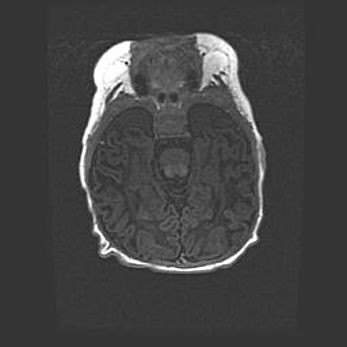

Множественные кисты обоих полушарий головного мозга, наибольшая из них в правой затылочной области. Ассиметричная атрофическая гидроцефалия.

Возраст: 7 месяцев

Вес: 5660 г

Пол: мужской

Окружность головы: 41,5 см

Срок гестации: 28-29 недель

Кисты головного мозга развиваются в результате многоочаговых некрозов вещества мозга и возникают вследствие перенесенной перинатальной инфекции, менингитов, энцефалитов, асфиксии, родовой травмы, расстройств мозгового кровообращения различного генеза. Образованию кист в веществе головного мозга плодов и новорожденных способствуют такие факторы, как высокое содержание в нем воды, недостаточная (или отсутствие) миелинизация и слабая астроглиальная реакция на повреждение.

Кисты могут сочетаться с гидроцефалией и другими поражениями головного мозга.